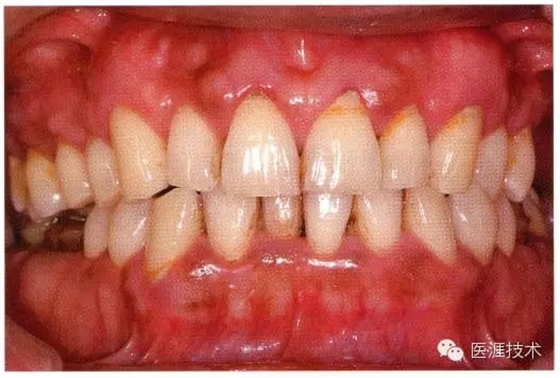

44歲牙周炎女性的臨床照片

640.webp (17).jpg

44歲患有糖尿病病史(未治愈)。菌斑控制不良。通過牙周探診,全頜有4~8mm的牙周袋,在X光片中可以看到上頜前牙處中度牙槽骨吸收,磨牙處重度牙槽骨吸收。二次齲齒和根面齲齒也有發(fā)生??梢钥吹礁∧[性腫脹,收到刺激后會(huì)出血。